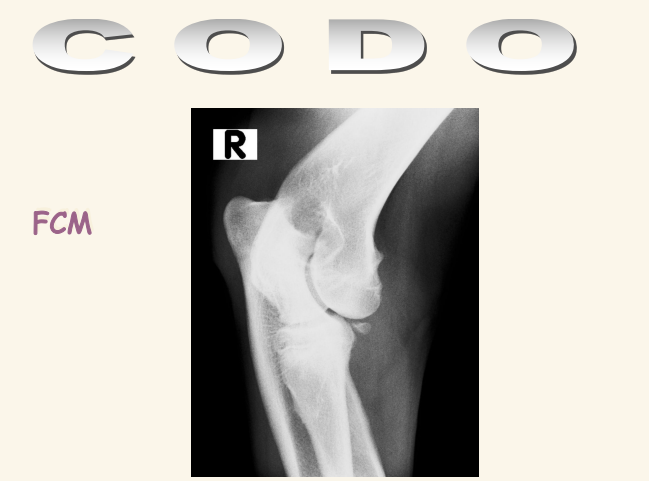

- FCM: Fragmentación del Coronoides Medial, una de las lesiones típicas de displasia de codo